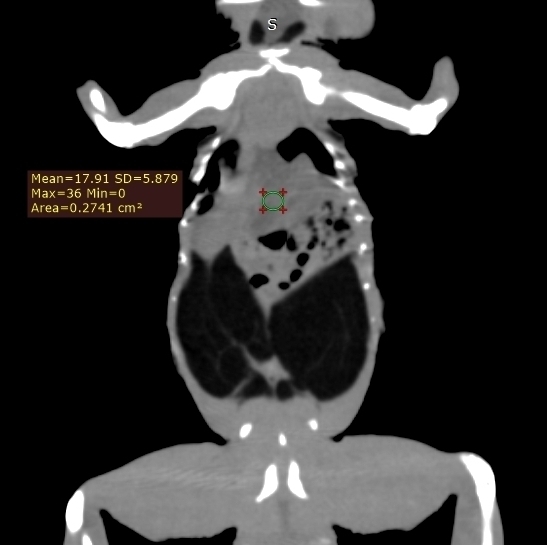

Компьютерная томография на сегодняшний день представляет собой наиболее информативный метод визуализации для диагностики липидоза печени у пресмыкающихся, включая ящериц2,12,13,19. Данный метод позволяет количественно измерять рентгенологическую плотность в единицах Хаунсфилда (HU), основываясь на поглощении рентгеновских лучей различными тканями8. Плотность печени менее 20 HU коррелирует с наличием умеренного липидоза печени у бородатых агам и других видов ящериц2,7 (фото 1-3) . Компьютерная томография оказалась высокоточным методом диагностики липидоза печени у бородатых агам как с умеренной, так и тяжелой степенью заболевания. Была выявлена линейная корреляция между плотностью печени, измеренной в единицах Хаунсфилда, и результатами гистологического анализа образцов печени. Увеличение содержания жира в печени на 10% соответствовало уменьшению плотности печени на 4 HU2.